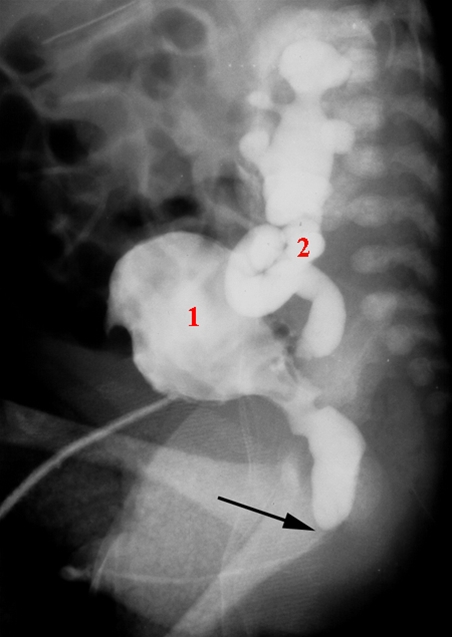

Urethraklap (miktionscystourethrografi)

Miktionscystourethrografi, røntgensidebillede

Obstruerende urethralklap (pil) med resulterende udvidelse af urinvejene herover samt udfordret og fortykket blæredetrusor (1) samt urinrefluks til de udvidede slyngede uretheres (2)

Kontrasten er sprøjtet ind gennem et efterfølgende afklemt suprapubisk kateter

- Vesica urinaria

- Uretheres